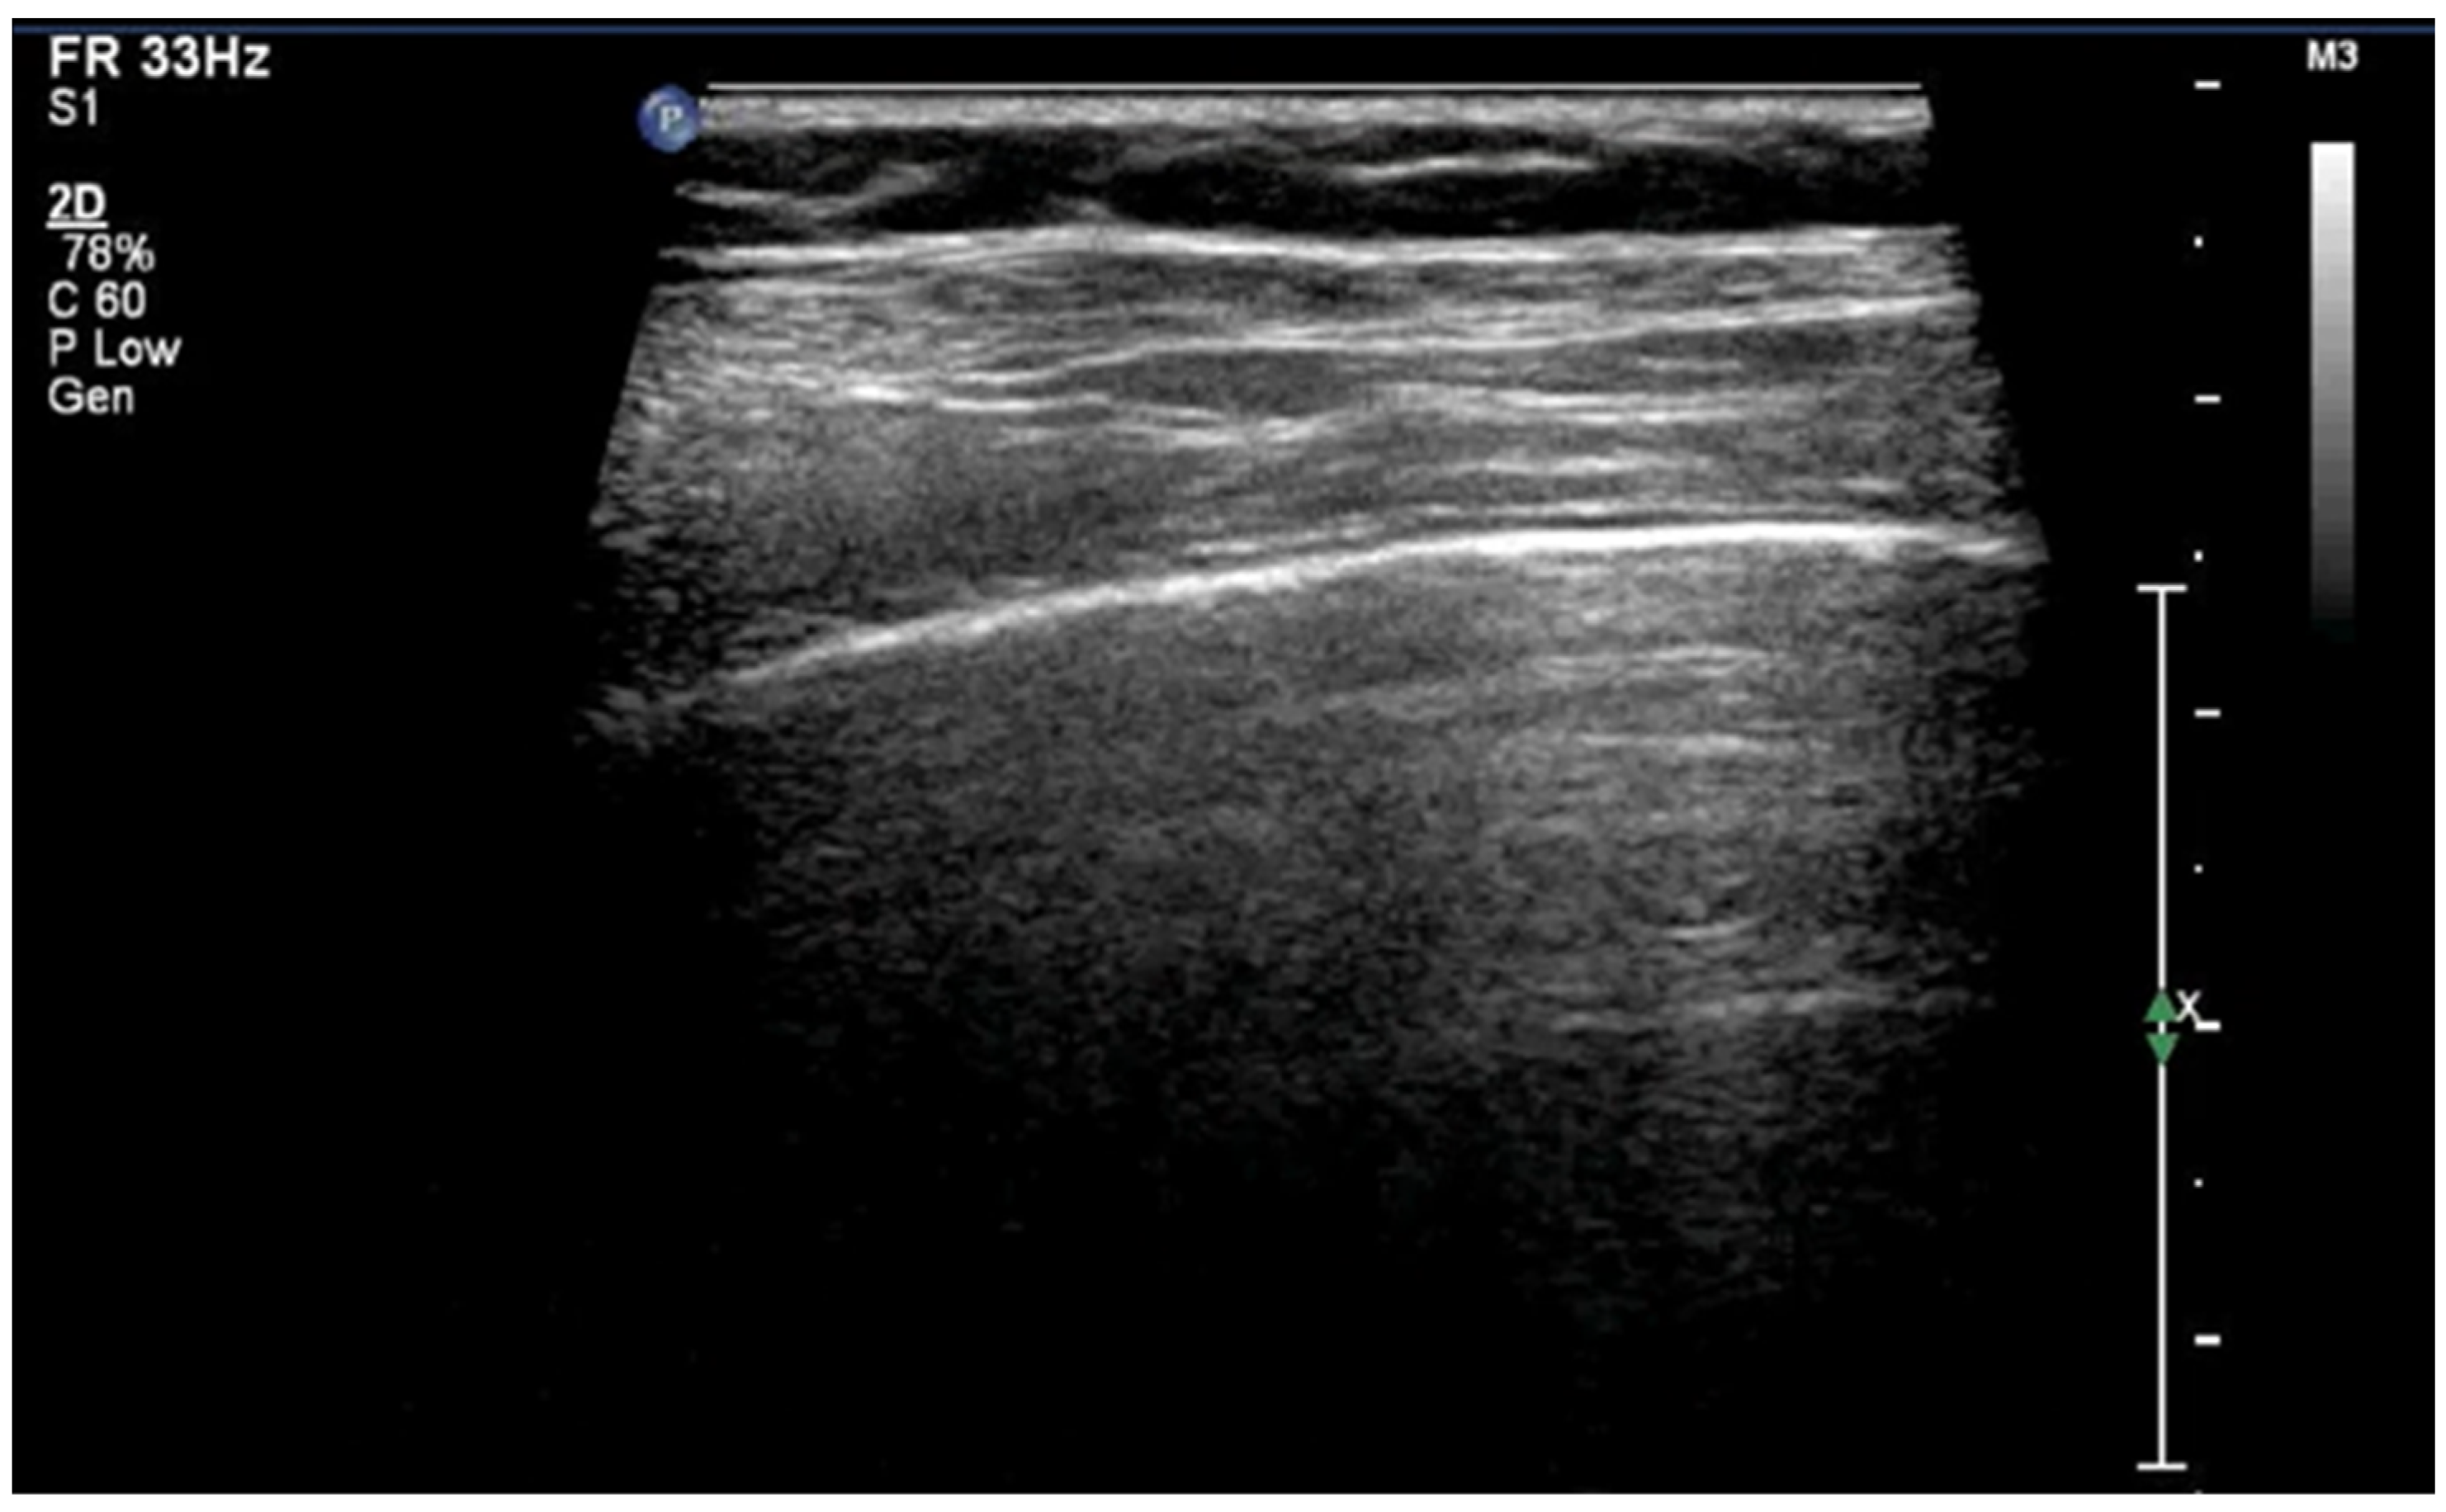

3.1.5. Sea-Shore Sign

The “sea-shore sign” is a characteristic ultrasound finding observed during M-mode (motion mode) scanning, and is indicative of normal lung sliding. In this pattern, the pleural line and overlying chest wall structures produce a series of horizontal echogenic lines, representing static tissues (Figure 6).

Figure 6.

Upper image: LUS with normal A-Lines in B (bright)-mode. The simultaneous M (motion)-mode image (lower image) reveals series of horizontal echogenic lines which represent the pleural line and its reverberations (A-lines), as well as the air-filled alveoli with a granular/sandy appearance (more prominent in real time scan). These in combination produce the seashore sign.

In contrast, the underlying lung parenchyma, which moves in synch with respiration, generates a granular or sandy appearance due to the dynamic motion of air-filled alveoli [17]. This combination creates the visual effect of waves (static layers) above and sand (with a dynamic speckled texture) below, thus producing the so-called “sea-shore sign”. The presence of this sign confirms normal apposition and movement of the visceral and parietal pleurae, and can be used to effectively rule out pneumothorax at the examination site. The “sea-shore sign” is considered to be a reliable and non-invasive indicator of intact lung sliding, and is frequently used in both adult and neonatal lung ultrasound to assess respiratory function and pleural integrity [5,6,15,22,23].